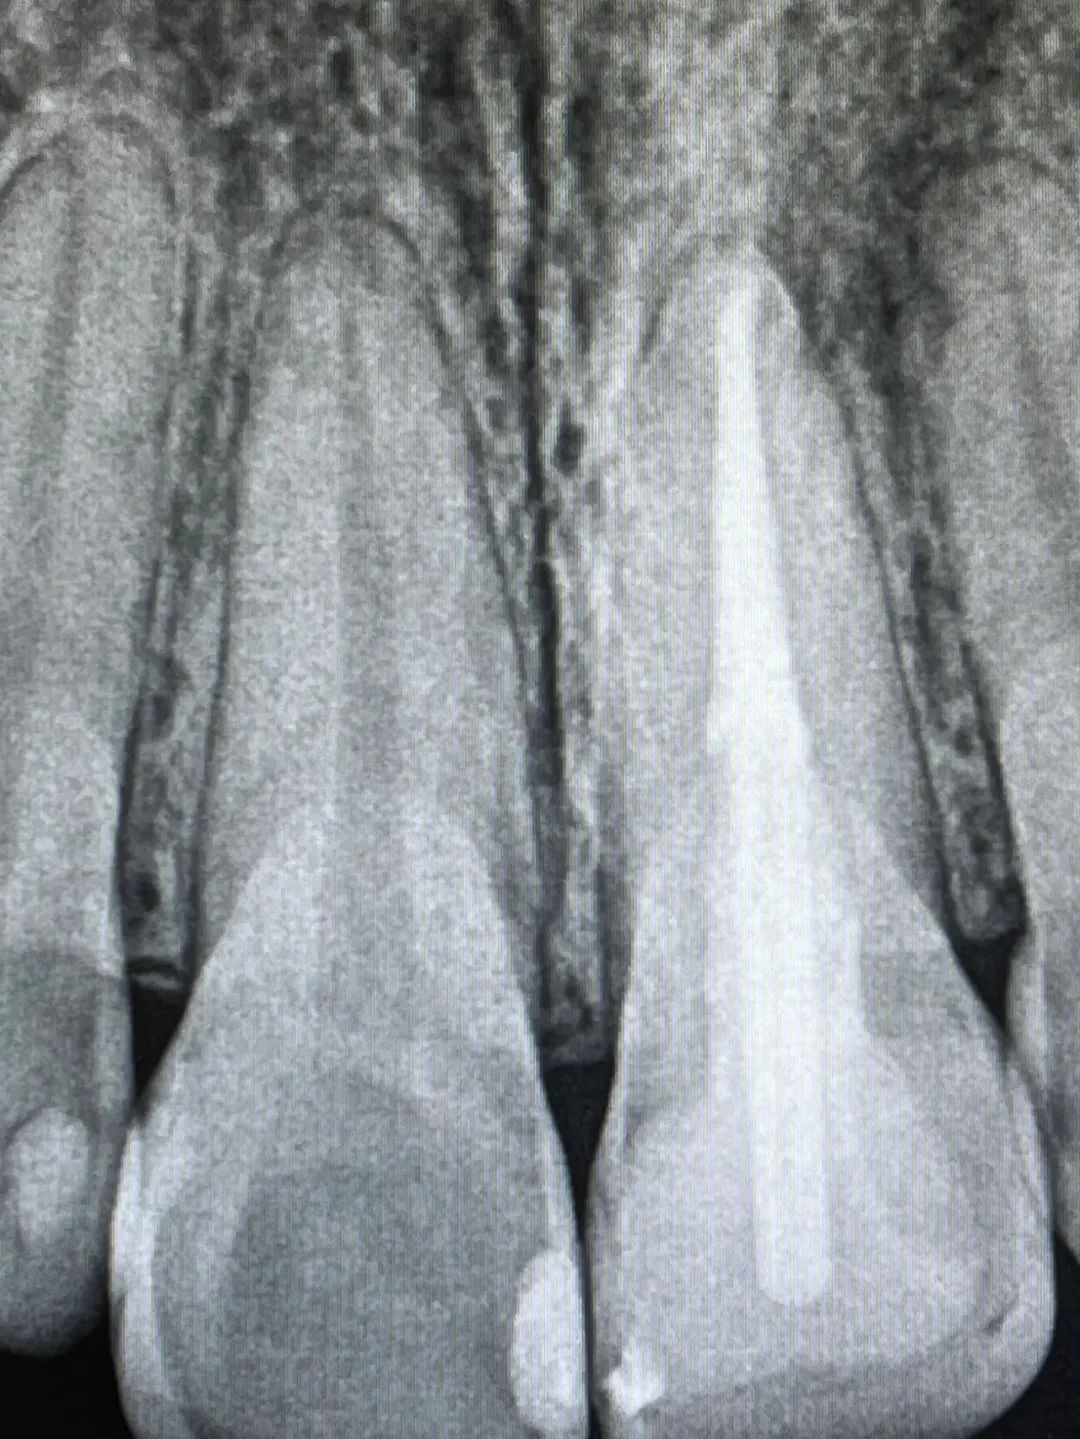

陈某,28岁,3年前因左上前牙因龋坏严重在外口腔门诊就诊后被告知龋坏严重需“根管治疗”,治疗后行树脂充填修复,期间无不适,近1年来发现患牙变色严重、未及时处理,愈发严重,现前来我院口腔科就诊。经完善口腔检查后发现21号牙着色严重,舌侧窝、近远中边缘嵴均有牙色充填体,打开后发现牙体髓腔内有大量腐质和污染的充填物;X线根尖片显示近远中、舌侧窝有充填体洞底暗影明显,根管内充填物不密实和不到位、根尖区阴影4×4mm。诊断为:21慢性根尖周炎、内源性着色牙、继发龋、牙体缺损。治疗计划:①21根管再治疗+内漂白术+纤维桩+复合树脂充填;②21根管再治疗+内漂白术+纤维桩树脂核+全瓷冠修复;③21根管再治疗+内漂白术+纤维桩树脂核+瓷贴面修复。知情同意后患者先选择方案①。经过6次显微诊疗后着色牙里里外外都变动非常干净,颜色也逐渐恢复到与邻牙接近,经5个月的随访根尖区的炎症也基本消退。

术前根尖片

术后根尖片